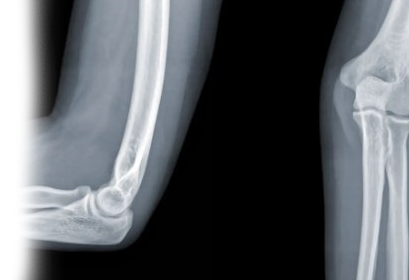

Рентгенография локтевого сустава – важный метод прицельного исследования, который позволяет оценить состояние локтевого сустава. Диагностическая услуга выполняется в двух проекциях.

Рентген позволяет исключить патологию локтевого сустава костно-травматического, дегенеративно-дистрофического, опухолевого генеза.